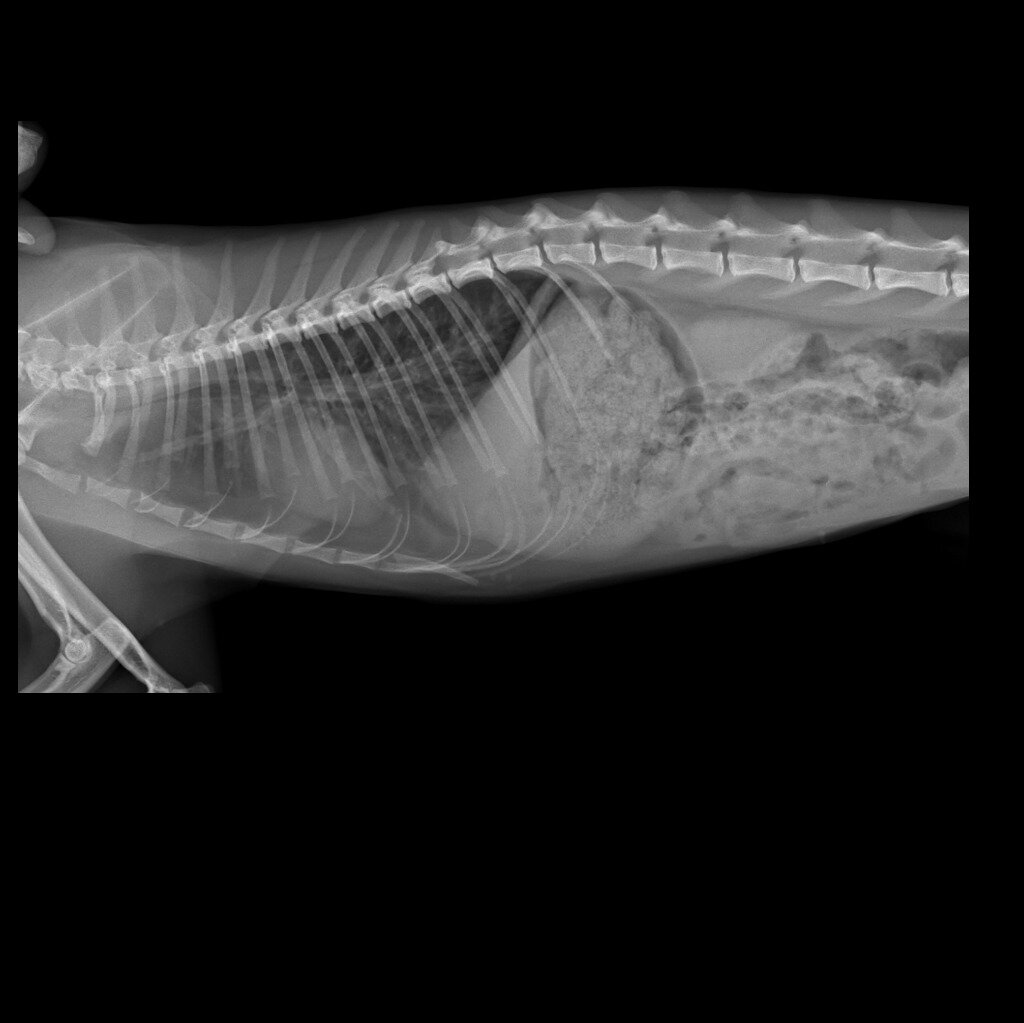

Друзья, 22.03. носила двух кошек и одного котика на кастрацию в ветклинику" Умка". Одна из них была Кобра. Она ко мне попала в ноябре 23 г-тяжело дышала, задыхалась. Рентген показал, что у кошки был сильный ушиб грудной клетки, в легких жидкость на уровне паха кровавое мессиво. Кошечка прошла длительное леченик, а попутно и пережила холода в тепле и безопасности. У кошечки всё было хорошо, но меня смущал периодический надрывный сильный кашель. Сделали ей повторный рентген и была запланирована кастрация. В кастрации нам отказали (пока), потому что кошечка во время введения наркоза может уйти на Радугу. Хорошо, что я ее не глистогонила всё это время. Меня смущал кашель, а т к у меня уже были сердечники, такую процедуру нужно делать очень аккуратно или можно потерять кошечку.

Рентгеновский снимок показал патологию сердца. По снимку видно, что сердце лежит на легком, так не должно быть. Врожденная или приобретенная патология, пока сказать не можем. А в последние дни приступы кашля участились, что меня пугает. Предварительный диагноз - подозрение на патологию сердца и астму. Кошечке назначено пройти УЗИ сердца. В понедельник ее запишем на обследование. Запись за 2-3 недели.